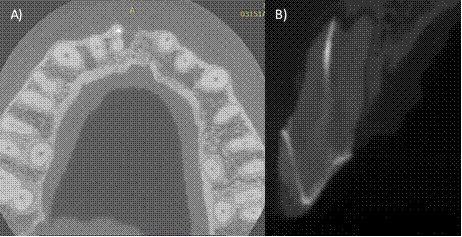

Upon clinical examination, we observed swelling of the tissues in the anterosuperior area and the presence of sinus tract, a misadjusted restoration corresponding to a metal-free crown, invasion of the biological width, gingival inflammation, chewing pain, horizontal and vertical percussion (Fig. 1B). In the periapical X-ray of the dental organ #11 (ortho-radial and mesio-radial), we observed a radiolucent lesion in the root at the apical and mesial level, loss of the interproximal bone crest, and non-visible lamina dura. In the apical portion, an underfilling was observed (Fig. A,C). A CBCT was performed, and the CT scan confirmed that there were two roots in said dental organ, and that only the vestibular root was endodontically treated (Fig. 2 A-B). Diagnosis: Dental organ previously treated, with chronic apical abscess (29. Anesthesia was administered supraperiosteally using 4% articaine with epinephrine 1: 100,000 in cul-de-sac anesthetizing the anterior alveolar nerve. The coronary restoration was removed using a diamond bur and high-speed handpiece, and once removed, absolute isolation was achieved with a rubber dam. Then, the gutta-percha was removed with Wave One Gold files (Dentsply Sirona, Tulsa Dental), the palatal canal was explored with type K 6 and 8 files until it was permeabilized, the working length of both roots was obtained with the help of the Apex ID apical locator (SybronEndo, Orange, CA) (Fig.3 A). It was performed with Wave One Gold files (Dentsply Sirona, Switzerland) Large (45/05) for the vestibular canal, and medium (35/06) for the palatal canal, irrigation was performed with hypochlorite at 5.25% throughout the treatment to finish with an irrigation protocol of three cycles of 20 seconds, sodium hypochlorite 5.25%, distilled water and EDTA 17% (Smear clear Sybron Endo, CA), activated with ultrasound (Ultra X, Eighteeth Medical). Calcium hydroxide was placed as intra-ductal medication for 15 days.

Figure 2: A) Axial section of the CT scan, two roots belonging to dental organ #11 are observed, the vestibular root shows obturation material, but the palatal root was not treated, B) Sagittal section where a permeable palatal canal can be seen.